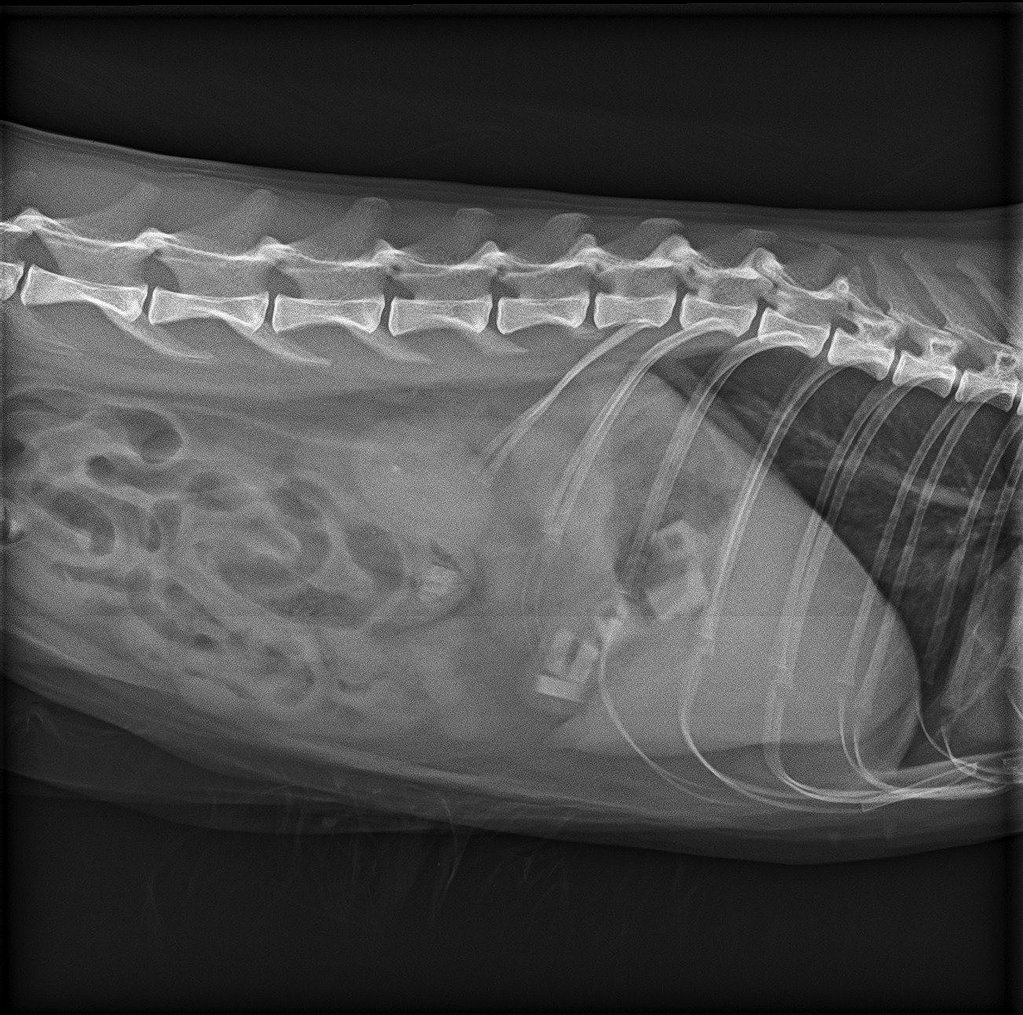

Nadat ze een deel van de rubbertjes had uitgebraakt werd een röntgenfoto gemaakt om te controleren of ze alles had uitgebraakt. Op onderstaande foto is zichtbaar dat dit niet het geval was.